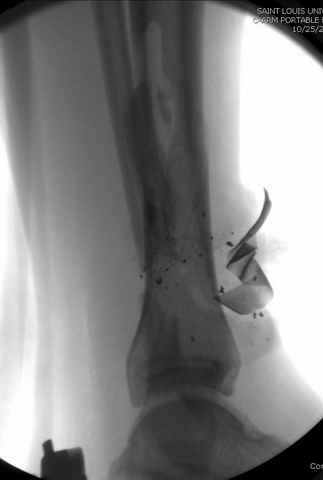

На снимках варианты фиксации малоберцовой:

№ 6-11 при pilon percutaneus fixation

DK> № 6-11 при pilon percutaneus fixation

А если без? Результат был бы хуже?